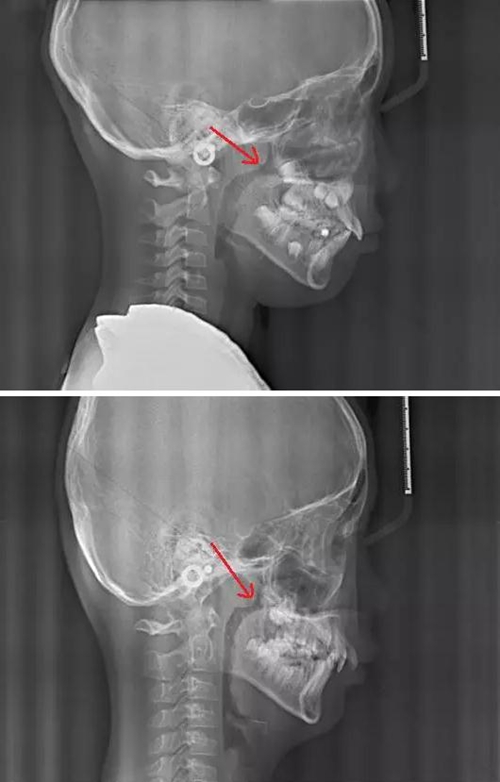

賀老師提到兒童青少年最常見的兩種阻塞呼吸道的問題即腺樣體肥大和扁桃體肥大。首先我們通過頭顱側位片來了解一下這兩個腺體在x線片上的位置。

以下兩張標注的是肥大的腺樣體及其位置